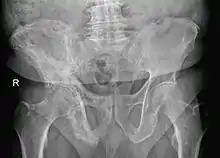

Paget's disease of bone is a bone disease in which excess bone formation results in weak bone deformities and an increase risk of broken bone.[1] Usually there are no symptoms.[1] It can affect one or more bones, with the most frequently affected sites being the hip, lower leg, upper leg, back, and skull[1] Symptoms include bone pain, joint pain, nerve problems, and difficulty breathing due to associated heart problems.[1]

The disease is progressive and slowly worsens with time, although people may remain minimally symptomatic. Treatment is aimed at controlling symptoms, but there is no cure. Any bone or bones can be affected, but Paget's disease occurs most frequently in the spine, skull, pelvis, femur, and lower legs. Osteogenic sarcoma, a form of bone cancer, is a rare complication of Paget's disease occurring in less than one percent of those affected. The development of osteosarcoma may be suggested by the sudden onset or worsening pain.